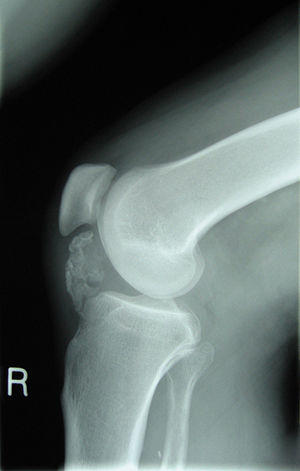

Osteochondroma X-ray.jpg

Lateral radiograph of the knee demonstrating ossification in the peritendinous tissues in a patient with osteochondroma.